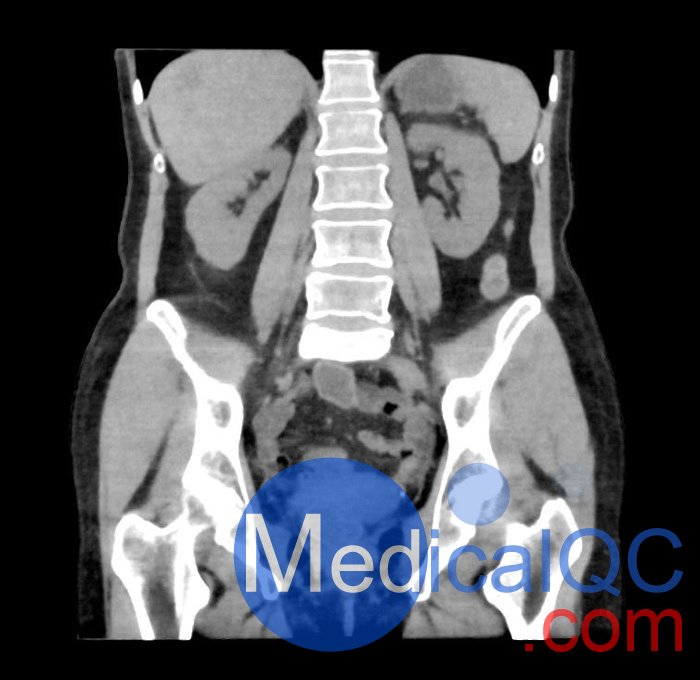

WEK55-02腹部骨盆模体,WEK55-02腹部骨盆模型模拟腹部和骨盆,无需静脉注射造影剂(天然)。它覆盖了会阴的第一腰椎。

它有胰腺肿块和肝脏病变。

该模型可用于 CT(包括 CBCT)以评估和优化成像性能和后处理应用,包括支持 AI 的应用。它也适用于培训目的。

该模型提供了对软组织和骨组织的详细而逼真的模拟。空隙中填充着约-160HU的纤维素-聚合物复合材料。

真实模拟骨骼和软组织,包括肝脏、胆囊、胰腺、脾、肾上腺、肾、胃、小肠、结肠和膀胱。

• 胰腺肿块。

• 肝脏病变。

WEK55-02腹部骨盆模体,WEK55-02腹部骨盆模型成像效果图: